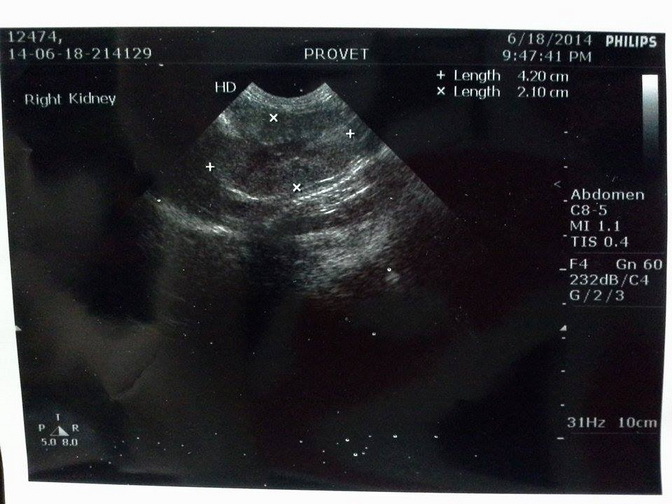

主題: 路倒的愛滋腎衰竭貓 (達叔) 申請者姓名: 徐慕雯 花色: 申請日期: 2014-07-06 03:45:06 申請者部落格: 申請者臉書網址: https://www.facebook.com/cocohsu.1104 所在縣市/合作醫院: 桃園縣/普羅動物醫院 治療費用: 12275元 需求人數: 14人 已結案 (2014-08-05 11:00:11) 報名人員: Evan VI、Ace Sky(已付款)、Cassidy Chen(已付款)、bobo Chang(已付款)、miraai、Puffy(已付款)、Victoria Liou x8(已付款)、vivian(已付款)、Irene(已付款)、 候補人員: Yaman、徐慕雯、 動物病情說明: 我餵養兩年的貓咪,前年已TNR。

送醫檢查出來有愛滋,腎衰竭,牙結石及口炎 ~~

經治療後,精神食慾都恢復許多,但是腎指數仍高居不下,所以牙結石及口炎的部份也無法麻醉洗牙處理。只能靠打皮下點滴及藥物來控制病情 ~

腎衰竭的情況有可能是愛滋病毒攻擊,也有可能是貓咪本身的慢性疾病,未來只能吃腎衰竭的處方飼料,及每日打皮下點滴......